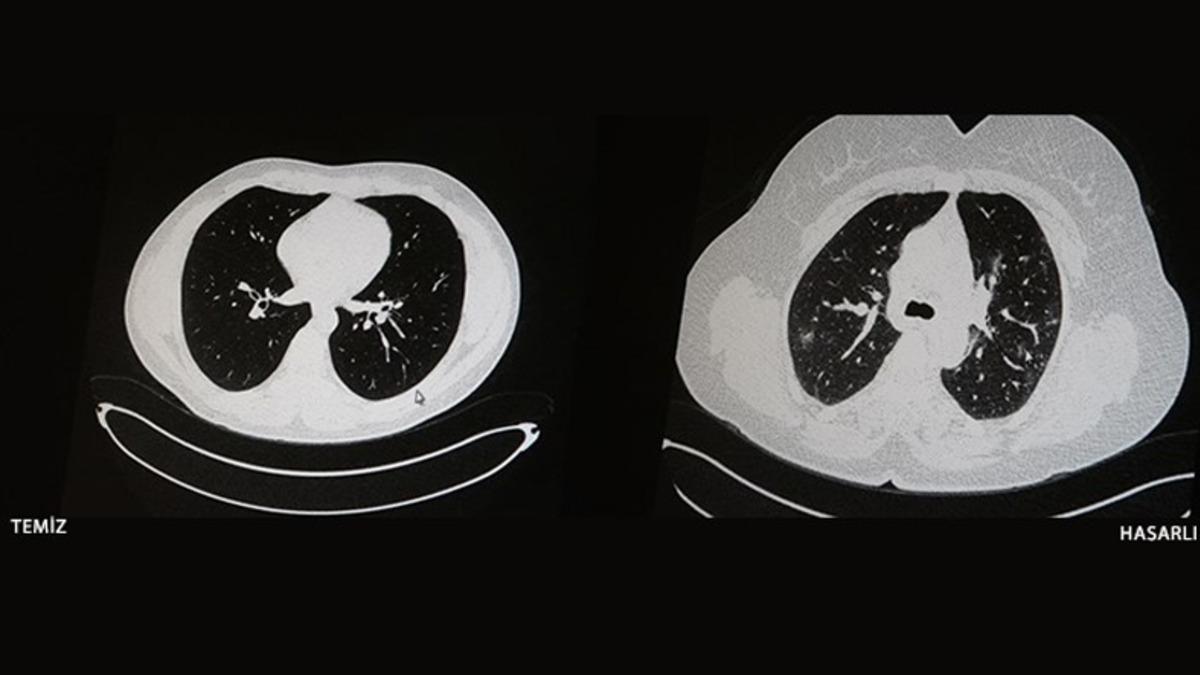

Söz konusu olay, Elazığ'da yaşandı. Öksürük, halsizlik ve yorgunluk gibi belirtilerle hastaneye başvuran iki gencin, aslında COVID-19'a yakalandığı tespit edildi. Bu gençler arasındaki en büyük fark, birinin aşılıyken diğerinin aşılı olmamasıydı. Gençlerin her ikisi için de akciğer tomografisi isteyen doktorlar, aşı olup COVID-19'a yakalanan gencin ciğerlerinde hiçbir sorun tespit edemediler. Aşısız olan genç ise koronavirüsün etkisiyle zatürreye yakalanmıştı.

İşte aşı olan ve olmayan COVID-19 hastalarının tomografi görüntüleri

Konuyla ilgili açıklamalar, Göğüs Hastalıkları Uzmanı Dr. Cebrail Azar tarafından yapıldı. Çekilen tomografi görüntülerinin aşı olmamanın nelere mal olabileceğini gösterdiğini söyleyen Azar, "Ben gencim, benim bağışıklık sistemim kuvvetli." algısına düşülmemesi gerektiğini ifade etti. Herkesin hastalığa yakalanabileceğini ancak önemli olan şeyin hasar olduğunu hatırlatan Cebrail Azar, herkesin aşı olması gerektiğini söyledi.